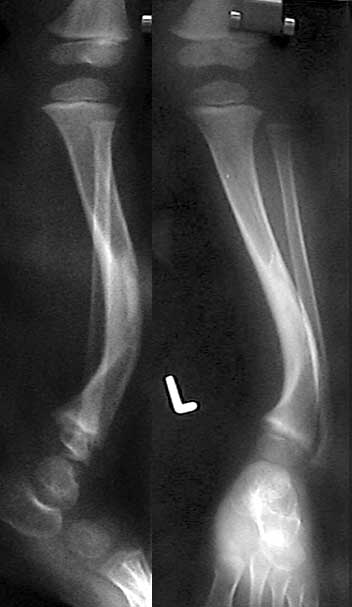

На консультативный прием родители привели ребенка 3 лет с деформацией левой голени.

Деформация была выявлена сразу после рождения ребенка и с его развитием усиливается хромота. При ходьбе ребенок полностью наступает на ногу, распределяя нагрузку на внешний край стопы.Нагрузка на ногу безболезненна, данных за травму или инфекцию нет. При осмотре кожных покровов отмечаются характерные пигментные пятна cafeau lait. Совокупность данных анамнеза и осмотра наводит на мысль о нейрофиброматозе с врожденным псевдоартрозом б\б кости. Рентгенограммы прилагаю. Заранее признателен за высказанные мнения по тактике лечения ребенка.С наилучшими пожеланиями,Евгений Чекашкин

Я тоже думал о фиброзной дисплазии. Просмотрел литературу по с-му Albright, представленные картинки демонстрируют кистозную трансформацию бедра или б\б, м\б костей с истончением кортикальной пластинки и как результат этого описывают патологические переломы. У этого ребенка по рентгенограммам наоборот кортикальный слой утолщен, а интраоперационно- костно-мозговой

канал полностью закрыт в зоне деформации.

Мы сделали остеотомию м/б кости и клиновидную резекцию на высоте деформации во фронтальной и сагитальной плоскостях с фиксацией Rush pin. Резецированную кость отправили на гистологию - ждем результата. После операционные рентгенограммы ещё не перегрузил на диск, но обязательно вышлю. Изначально планировали сегментарную остеотомию б/б кости для полной коррекции, но после резекции клина и фиксации стержнем клинически ось конечности выравнялась, учитывая возможные проблемы со сращением и достигнутую коррекцию, решили ограничиться вмешательством на одном уровне. Получим гистологию, подождем сращения и если будет необходимо, то спланируем более дистальную остеотомию б/б кости.